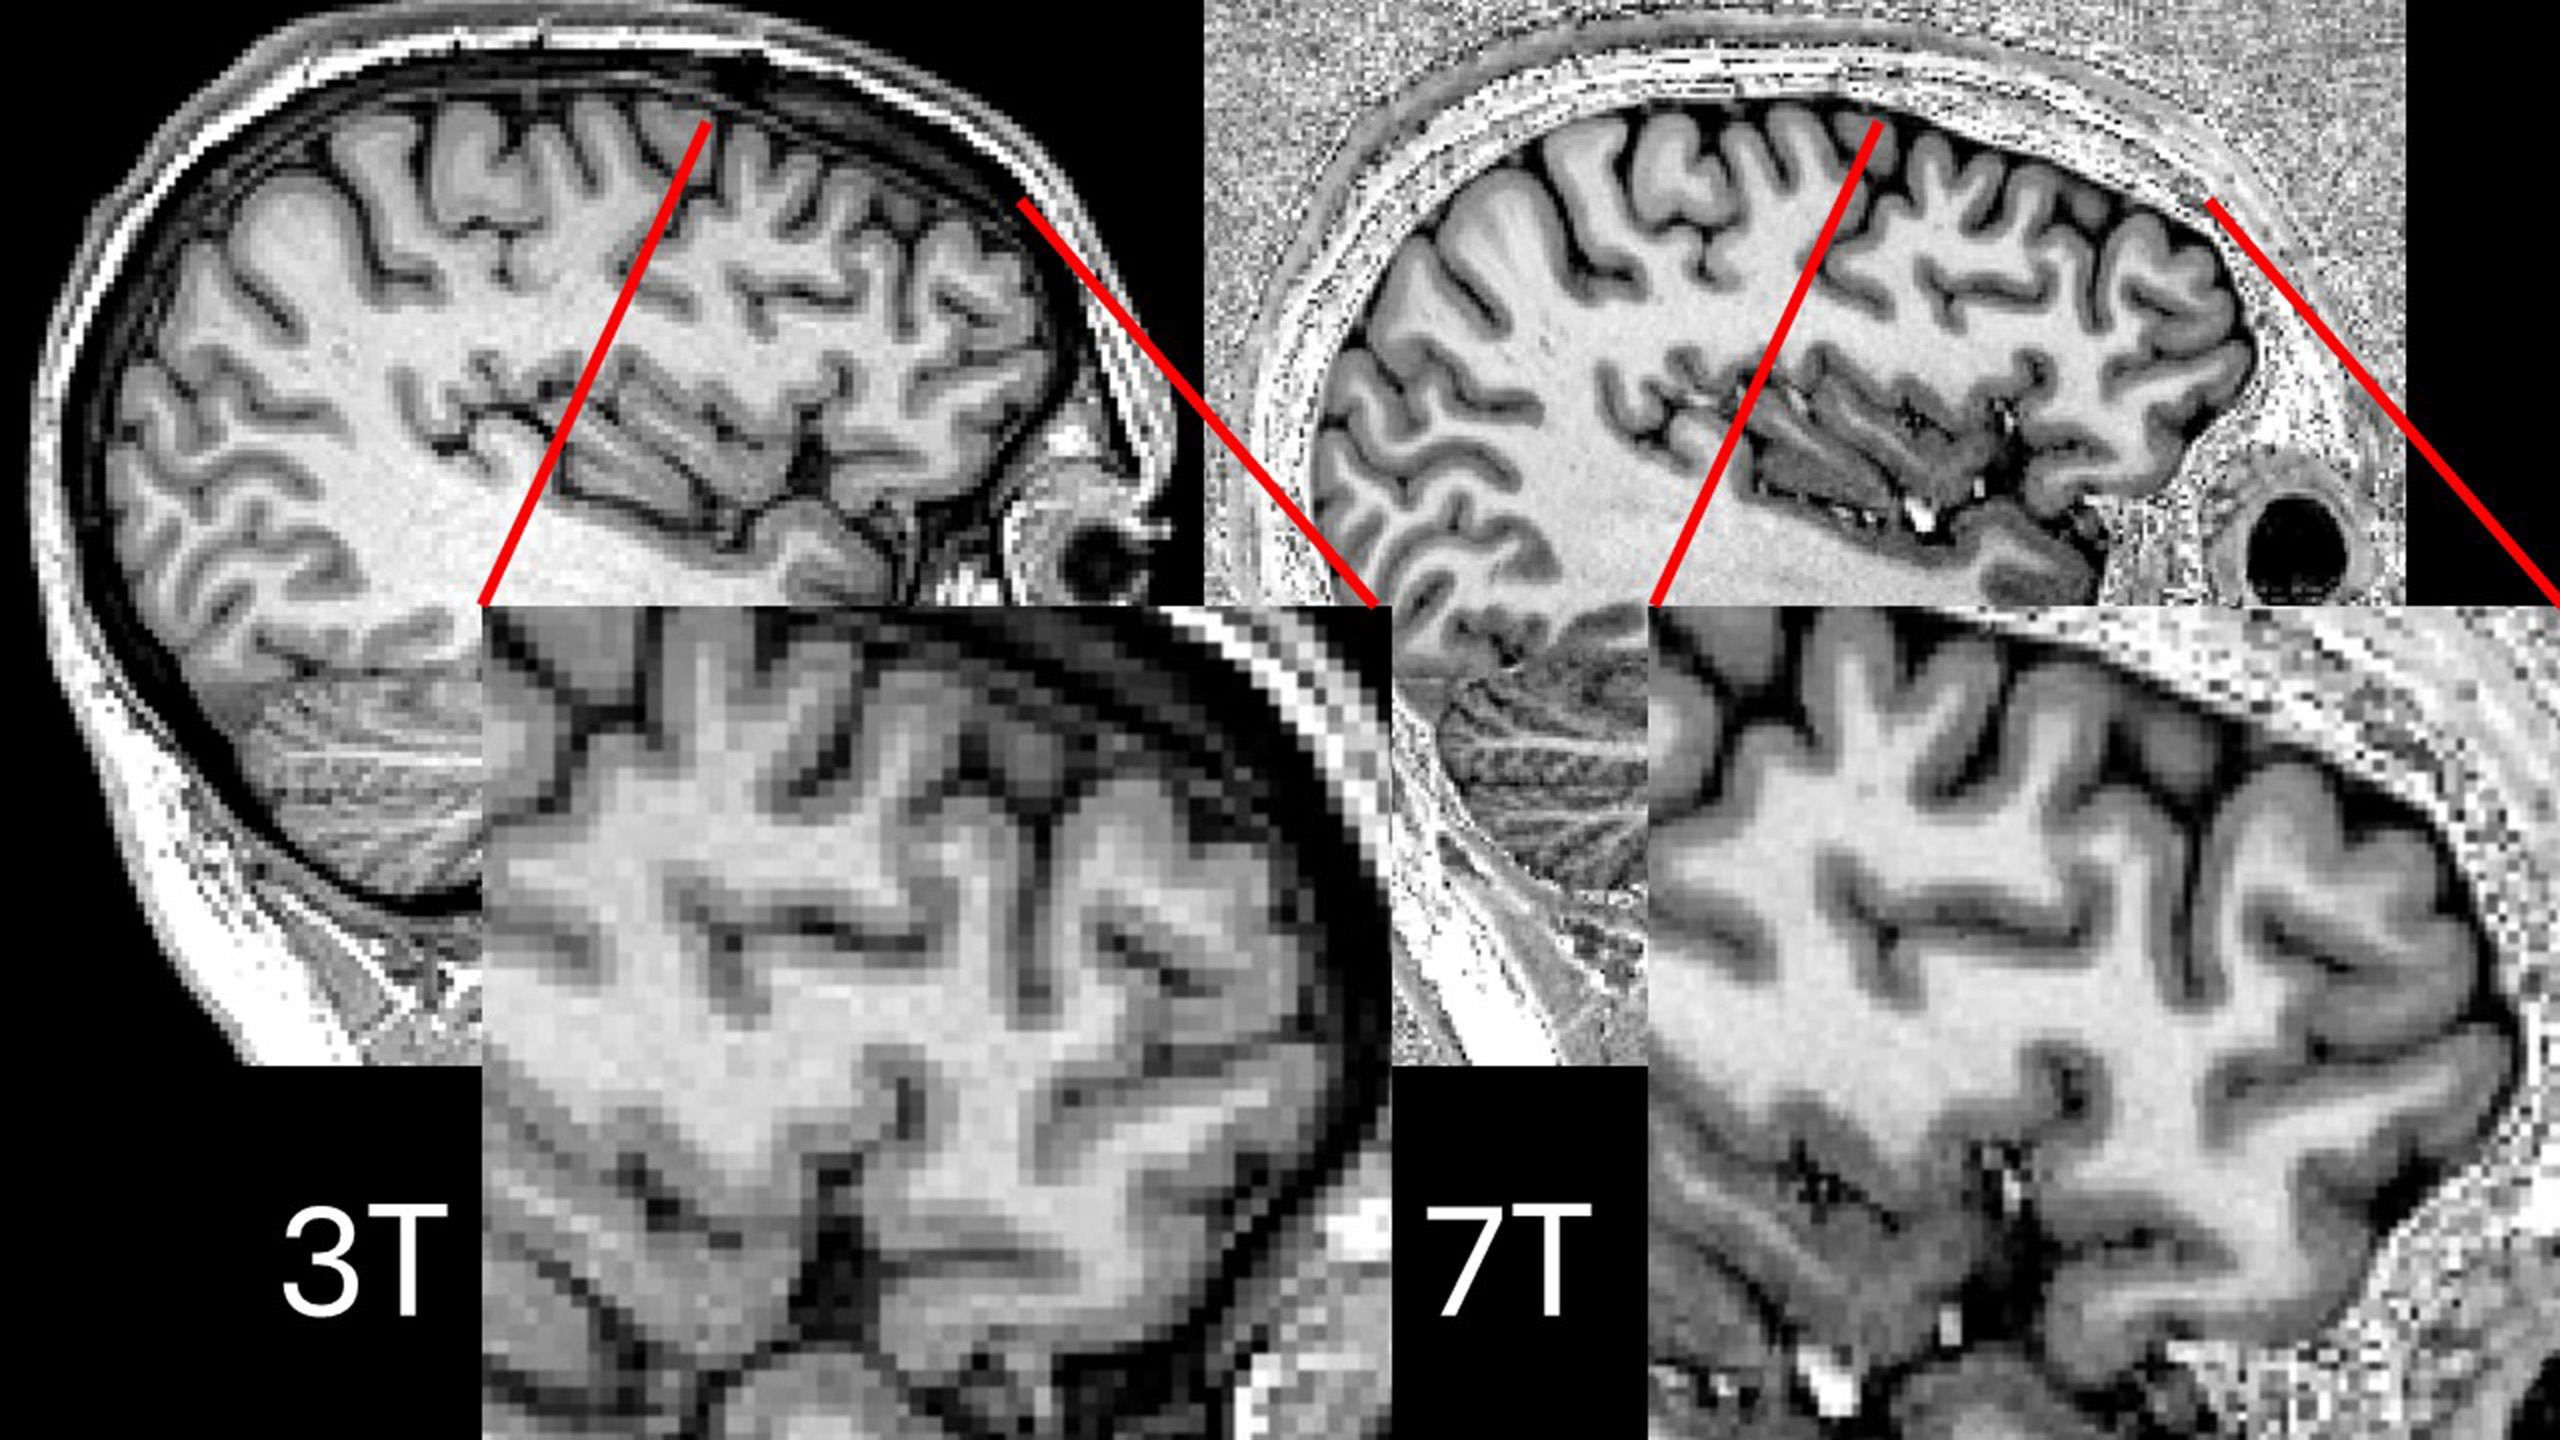

The researchers also evaluated 24 healthy control subjects who were matched for age and sex and were evaluated between April 2007 and December 2012. DTI-MRI was performed using a 3-tesla scanner (Tim Trio, Siemens Healthcare) to track the movement -- or diffusion -- of water in the brain's white matter.